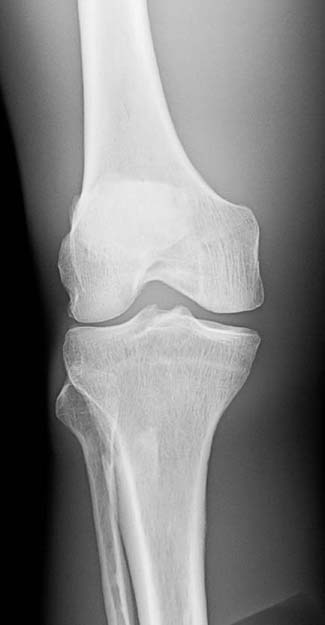

A radiographic image must have sufficient brightness to visualize the anatomic structures of interest (Fig. 3-13). A radiographic image that is too light has too much brightness to visualize the structures of the anatomic part (Fig. 3-14). Conversely, a radiographic image that is too dark has insufficient brightness, and the anatomic part cannot be well visualized (Fig. 3-15).The radiographer must evaluate the overall brightness in the image to determine whether it is sufficient to visualize the anatomic area of interest. He or she then decides whether the radiographic image is diagnostic or unacceptable.

FIG. 3-13 Brightness. Radiographic image with sufficient brightness. (From Johnston JN, Fauber TL: Essentials of Radiographic Physics and Imaging, ed 3, St. Louis, 2020, Mosby.)

FIG. 3-14 Brightness. Radiographic image with excessive brightness. Brightness altered with postprocessing. (From Johnston JN, Fauber TL: Essentials of Radiographic Physics and Imaging, ed 3, St. Louis, 2020, Mosby.)

FIG. 3-15 Brightness. Radiographic image with insufficient brightness. Brightness altered with postprocessing. (From Johnston JN, Fauber TL: Essentials of Radiographic Physics and Imaging, ed 3, St. Louis, 2020, Mosby.)